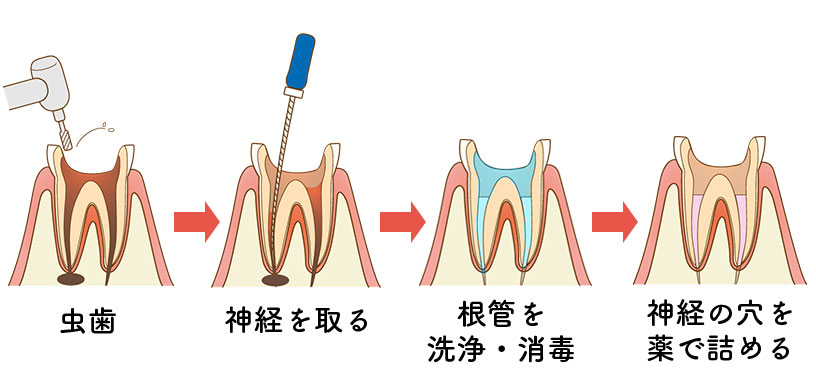

根管治療の具体的な治療内容

歯の根っこ(神経)の中から痛みや腫れの原因である「感染した汚染物」を、取り除く治療です。

針のような道具を使って、感染した汚染物をとりのぞいていきます。

汚れを取り除いた箇所をキレイに清掃・消毒して、お薬で埋めるまでが根管治療です。

歯の神経(歯髄)が残っている場合の治療方法は「抜髄」とよばれます。文字通り「歯の神経を抜く」治療です。

抜髄の流れ

- 麻酔をする

- 神経の入口まで歯を削る

- 針のような道具を使って、歯の神経を

取り除く - 神経をとった空洞を清掃、消毒する

- キレイになるまで繰り返す

(数回かかることがあります) - キレイになった神経の空洞に最終的なクスリを詰める

- レントゲン写真で状態を確認する

その後、歯そのものの修復をおこなっていきます。